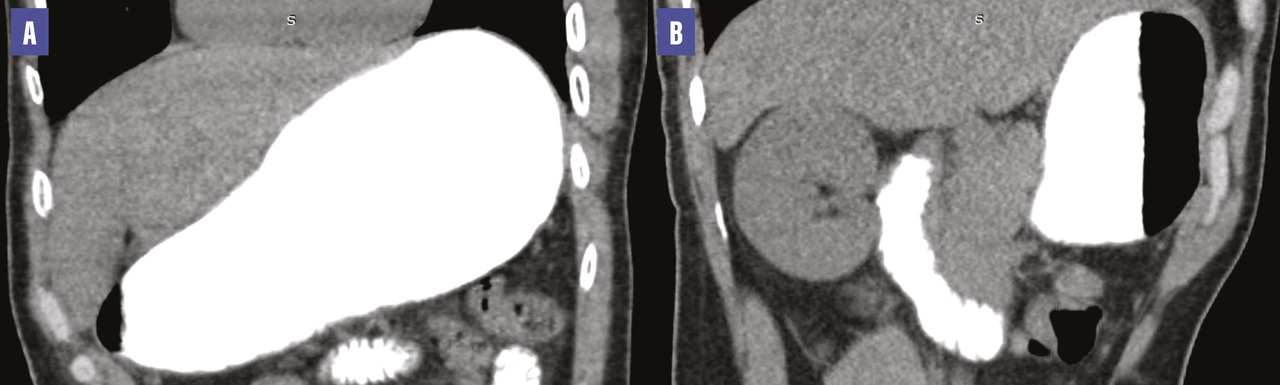

Une tomodensitométrie (TDM) abdominale met en évidence une compression de la troisième portion du duodénum par l’artère mésentérique supérieure associée à une importante dilatation de l’estomac et des deux premières portions du duodénum. L’angle aortomésentérique est mesuré à 12,2° et la distance aorte-artère mésentérique supérieure atteint 4,27 mm (fig. 1 et 2 ), ce qui a permis de poser le diagnostic du syndrome de la pince aortomésentérique.

Une tomodensitométrie (TDM) abdominale met en évidence une compression de la troisième portion du duodénum par l’artère mésentérique supérieure associée à une importante dilatation de l’estomac et des deux premières portions du duodénum. L’angle aortomésentérique est mesuré à 12,2° et la distance aorte-artère mésentérique supérieure atteint 4,27 mm (

Ce syndrome implique l’utilisation de modalités d’imagerie spécifiques. Les examens de référence sont le transit œsogastroduodénal (TOGD) suivi d’un scanner injecté. En fluoroscopie, les signes distinctifs sont les suivants : dilatation des première et deuxième parties du duodénum, éventuellement associée à une dilatation gastrique, et rétrécissement brusque de la troisième partie du duodénum, caractérisé par un défaut vertical linéaire en forme de bande recouvrant la colonne vertébrale. Le flux antipéristaltique de baryte proximal à l’obstruction est mieux visualisé en position couchée, genou-poitrine, ou en décubitus latéral gauche. Le scanner injecté permet de visualiser une compression en bec de la troisième partie du duodénum entre l’AMS et l’aorte, avec des critères spécifiques tels qu’un angle aorto-AMS inférieur à 22 à 25° dans le plan sagittal et une distance aorto-AMS inférieure à 8 mm.